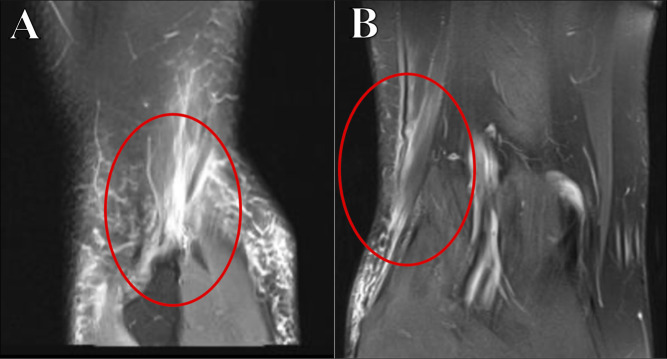

腿筋损伤是运动员常见的损伤,大多数损伤发生在肌肉腹部或近端肌肉肌腱连接处。远端腘绳肌病理相对不常见,但包括急性和慢性诊断的集合,可表现为膝关节内侧或外侧的症状,这是基于腘绳肌肌腱受累的情况。鹅肝粘液囊炎是最常见的远端腘绳肌病变,并伴有其他慢性诊断,包括腘绳肌内侧或股二头肌断裂。急性股二头肌骨折可以发生在孤立的方式,但大多数情况下发生在并发后外侧角损伤的高能创伤的结果。孤立性半腱肌破裂可发生在能量较低的急性事件中,通常发生在田径项目中。大多数远端腘绳肌病理可以不手术治疗,保守治疗效果良好。然而,急性撕脱伤往往需要手术干预,因为慢性问题不能充分响应长期保守治疗。由于远端腘绳肌损伤的发生率较低,因此远端腘绳肌损伤的治疗方法不如近端腘绳肌损伤发达。这篇综述的重点是远端腘绳肌损伤,目前的文献状态和治疗策略。

Hamstring injuries are a common injury sustained by athletes with most injuries occurring as strain injuries within the muscle belly or at the proximal musculotendinous junction. Distal hamstring pathology is relatively uncommon but comprises a collection of both acute and chronic diagnoses that can manifest with symptoms either on the medial or lateral side of the knee based on which hamstring tendons are involved. Pes anserinus bursitis is the most common of these distal hamstring pathologies with other chronic diagnoses, including snapping medial hamstrings or snapping biceps femoris. Acute biceps femoris ruptures can occur in an isolated fashion but most often occur in the setting of concomitant posterolateral corner injury as a result of high-energy trauma. Isolated semitendinosus ruptures can occur with lower-energy acute events, commonly with track and field events. Most distal hamstring pathology can be treated without surgery and do well with conservative treatment. However, acute avulsion injuries often require surgical intervention, as can chronic problems that do not adequately respond to prolonged conservative treatment. Treatment algorithms for distal hamstring injuries are less well-developed than more proximal injuries owing to their lower incidence. This review focuses on distal hamstring injuries, the state of current literature, and treatment strategies.